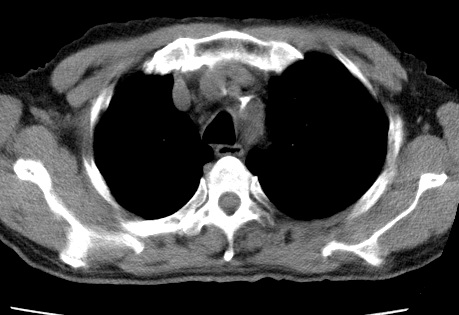

考虑右肺中叶不张,请大家发表意见

右肺中叶不张、肺门轮廓增大,占位不除外;建议增强,必要时支气管镜详查。

右肺中叶支气管闭塞,中叶肺不张,右侧肺门见肿块影。中心型肺癌的可能大。建议支气管镜检查。

右中叶体积明显缩小,且其支气管未显示,先考虑:中心型肺癌班右中叶肺不张。

建议:支气管镜检查。

右肺门旁类圆形肿块影,右肺中叶不张,建议纤支镜检查。

1右肺门旁类圆形肿块影,右肺中叶不张,建议纤支镜检查

2右侧胸膜增厚,右侧叶间胸膜区钙化

3右肺下叶小囊状透亮影考虑肺气肿